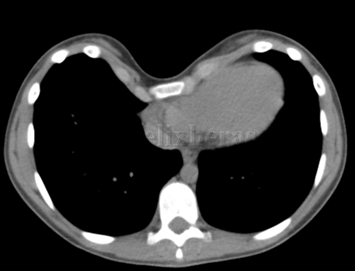

Técnica de Nuss